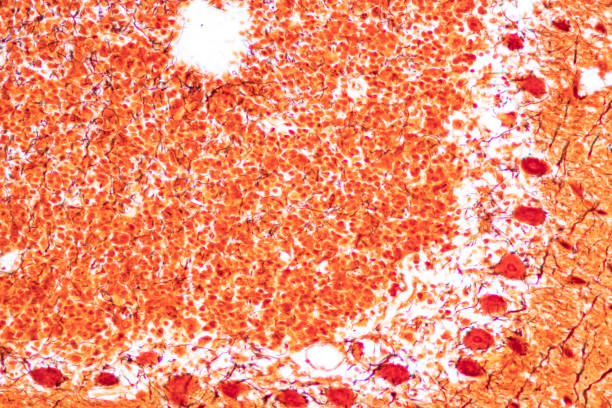

높은 요산수치는 먼저 신장에 부담을 줄 수 있습니다. 요산은 신장에서 처리되는데, 너무 많은 요산이 발생하면 신장의 부담이 크게 증가하게 됩니다. 이렇게 되면 신장 기능이 저하되고, 만성적인 신장질환의 위험성도 증가할 수 있습니다.